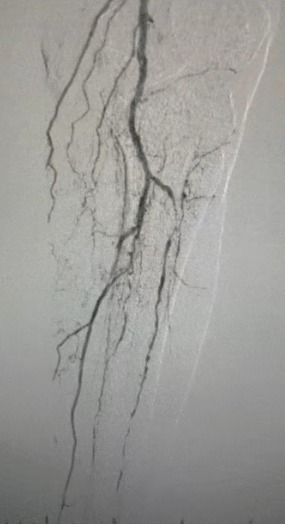

· Exame Físico: Pulsos femorais fracos; pulsos poplíteos e pediosos ausentes; ulceração no primeiro dedo esquerdo; necrose no primeiro e segundo dedos direito

· Imagem pré-operatória: estenose calcificada difusa grave em artérias bilaterais dos membros inferiores

Resultado cirúrgico

Pós-procedimento, a estenose arterial melhorou significativamente, o fluxo sanguíneo aumentou e a temperatura da pele aumentou. Nenhuma complicação pós-operatória ocorreu. Tanto o paciente quanto a equipe cirúrgica ficaram muito satisfeitos com os resultados.